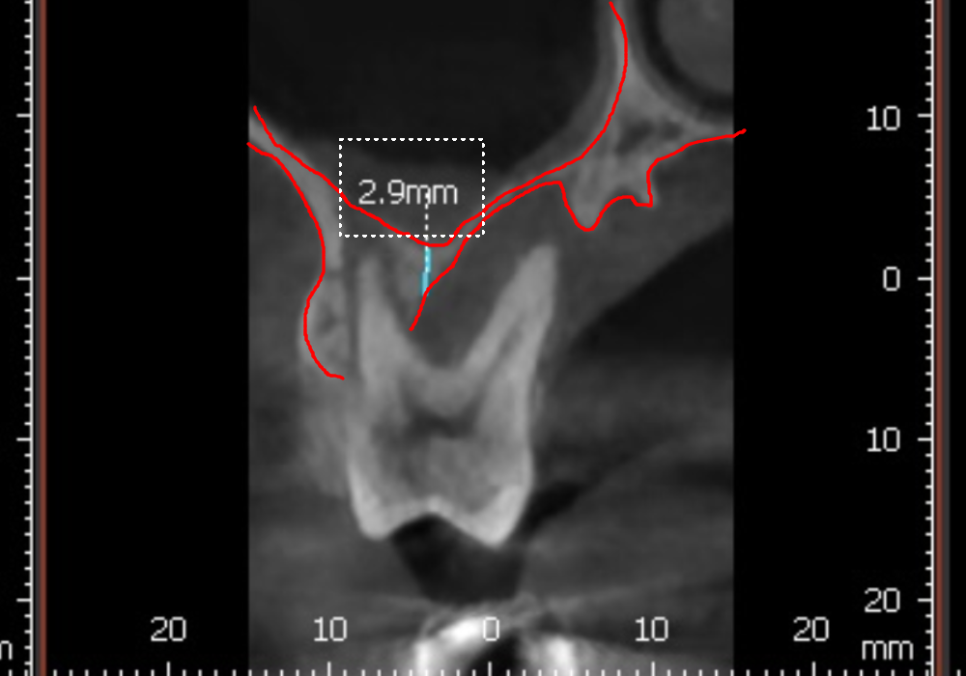

240327

CT로 확인해 보니 뒷니(#17) 역시

뼈가 이만큼이나 녹아 있었습니다.

앞에 치아와 비교해도 손색없을 정도로

뼈가 많이 사라진 상태였죠.

분명 파노라마 사진에서는

괜찮아 보였는데,

왜 CT에서는 이렇게 뼈가 녹은 게

확실히 보일까요?

그 이유는 파노라마는 1차원적인 평면 사진이라

상이 하나로 겹쳐 보일 수 있기 때문입니다.

반면 3D CT는 입체적인 사진이라

치아를 앞뒤 옆으로 돌려볼 수 있어

훨씬 자세하고 정확한 진단이 가능하죠.

보통 임플란트가 저작력을 버티려면

최소 7~8mm 이상의 뼈 길이가 필요한데,

환자분의 남은 뼈 두께는

고작 2.9mm였습니다.